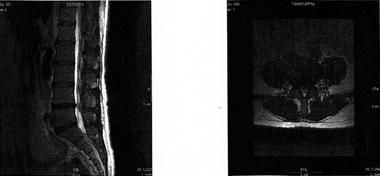

椎間板ヘルニア改善~川俣式骨盤整体法で再発を防ぐ方法

椎間板ヘルニアは、生活する上で支障のきたす障害です。